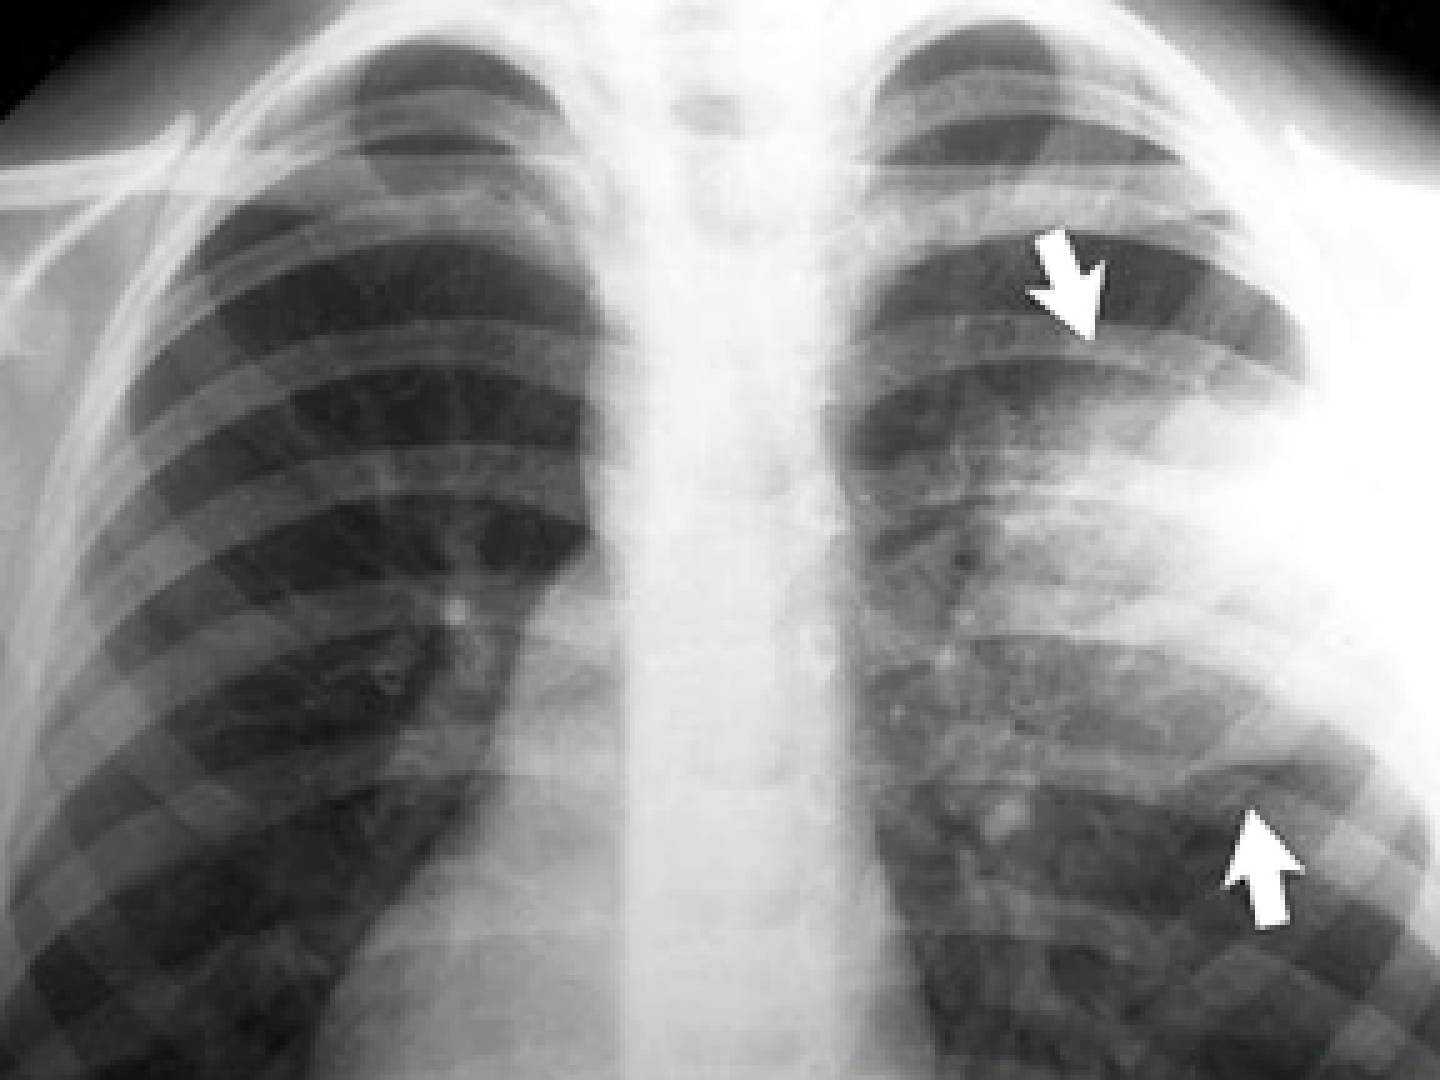

Интерстициальная пневмония на рентген снимке.

Интерстициальная пневмония

Такая разновидность пневмонии характеризуется поражением соединительной ткани, расположенной вокруг структур альвеолярного характера. Также страдает ткань кровеносных сосудов, находящихся в легких. Вот основные особенности интерстициальной пневмонии:

- корень легкого значительно расширяется;

- происходит перибронхиальная и периваскулярная инфильтрация, что практически всегда приводит к деформации сосудистого рисунка лёгких и к неравномерному его усилению;

- появляются полупрозрачные затемнения;

- появляются изменения, локализующихся внизу легких;

- иногда появляется тяжистость из-за уплотнения междольковых перегородок.